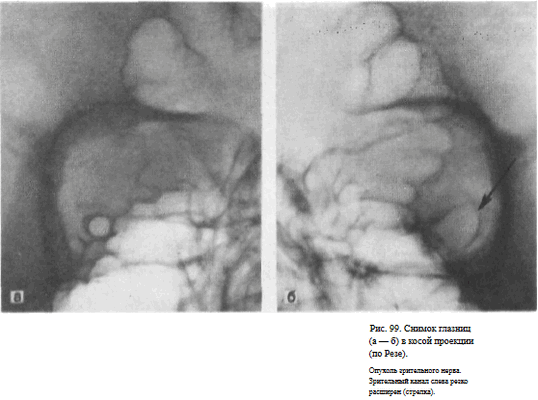

СНИМОК ГЛАЗНИЦЫ В КОСОЙ ПЕРЕДНЕЙ ПРОЕКЦИИ (СНИМОК ЗРИТЕЛЬНОГО КАНАЛА ПО РЕЗЕ)

Назначение снимка. Основное назначение снимка — получение изображения зрительного канала, Как правило, для оценки ширины и формы канала прибегают к последовательной съемке правой и левой глазницы.

Информативность снимка. На снимке отображается зрительный канал, имеющий обычно неправильно-округлую форму с четкими резкими контурами. Видны также вход в глазницу, решетчатые ячейки (рис. 98, а, б). Расширение зрительного канала, возникающее при опухолях зрительного нерва, как правило, может быть достоверно выявлено только путем сравнительного анализа снимков правой и левой глазницы (рис. 99, а, б). Поэтому снимки глазниц в косой проекции по Резе всегда следует производить с обеих сторон.

Изображение зрительного канала при правильной укладке проецируется вблизи наружной стенки глазницы в виде четкой кольцевидной тени.

Наиболее частые ошибки при выполнении снимка. При неправильном угле наклона головы и неправильной центрации пучка излучения отображение зрительного канала нечеткое. При грубом нарушении правил укладки зрительный канал на снимке неразличим.